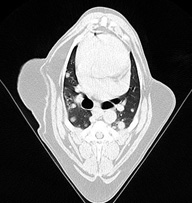

悪性腫瘍肺転移

• イメージ